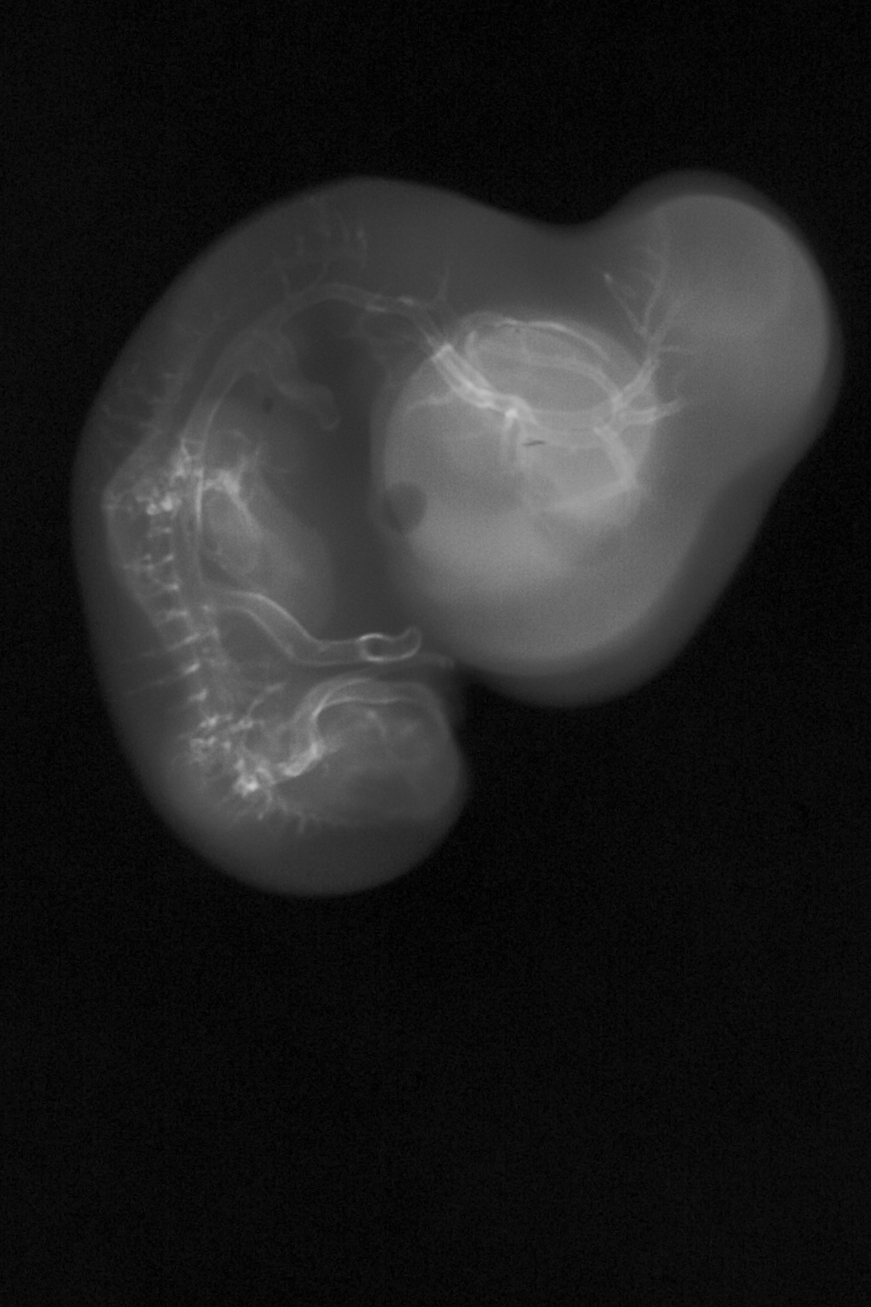

Chick Embryo Microangiography

Hamburger-Hamilton (HH) Stage 29 (approx. 6 - 6.5 days)

X-Ray Micrographs